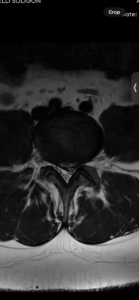

A hérnia de disco lombar é uma das causas mais comuns de dor nas costas e ciática. Ela ocorre quando o disco intervertebral uma estrutura de amortecimento entre as vértebras sofre uma lesão permitindo que o material gelatinoso interno núcleo pulposo se desloque para fora rompendo o anel fibroso externo. Esse deslocamento pressiona os nervos que passam por ali gerando dor e outros sintomas.

O diagnóstico é realizado pela correlação do quadro clínico com os exames de imagem.